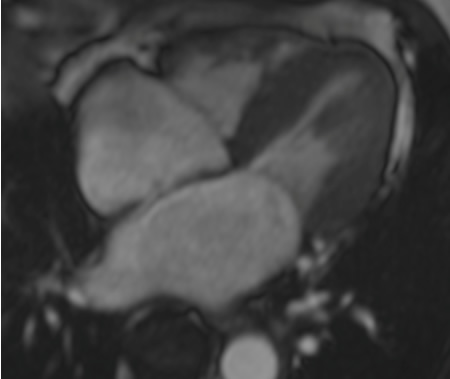

Ressonância nuclear magnética cardíaca (RNMC) exibindo cardiomiopatia restritiva com dilatação biatrial e hipertrofia ventricular esquerda concêntrica leve

Do acervo de Dr Jessica Webb; usado com permissão